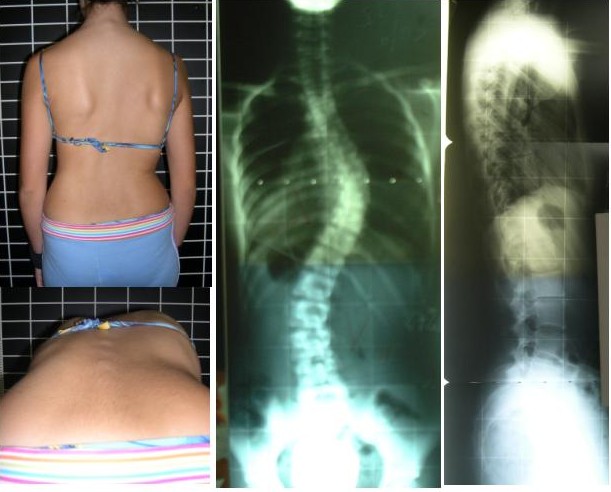

視診:

軽度側湾症の疑いがあるため、指標となる肩峰の高さ・肩甲骨の左右差・骨盤の傾斜を指標に観察。

右肩の挙上/右肩甲骨の外転変位/骨盤の左側方移動が確認できた。

⚫︎前屈時の左肋骨隆起(リブハンプ)がやや見られた。

⚫︎右腕を挙げると肩の挙上が顕著に視られる。

⚫︎立った状態で腰を左右に傾けると明らかに右側に倒しやすい。

そのためには骨格の稼働制限を矯正する方向を決めていかなければならない。この方の場合、胸椎(背中の部分)の右凸と腰椎(腰の部分)の左凸の側湾を伴っていた。